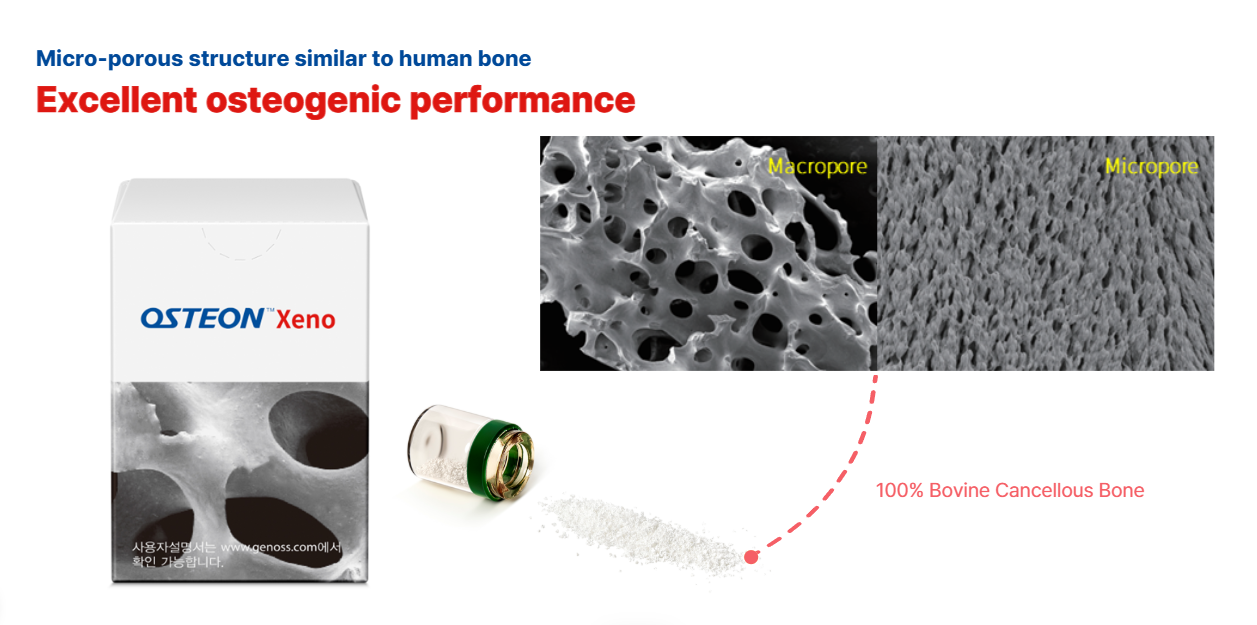

OSTEON™ Xeno is a deproteinized bovine bone graft offering excellent osteoconductivity with a highly interconnected porous structure.